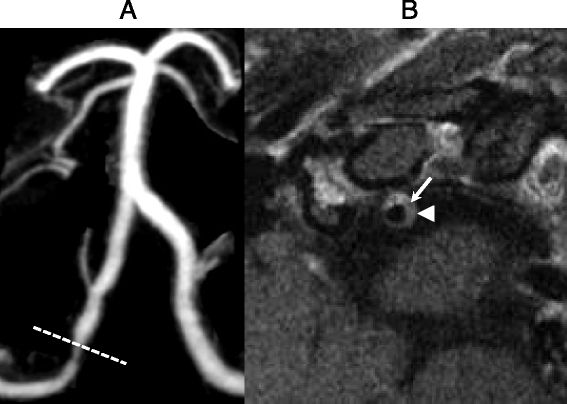

Maximum intensity reconstruction (MIP) from a contrast-enhanced MRA (a) and postcontrast 2D BBMRI (b) images through a right vertebral artery plaque in a 49 year old woman with multifocal intracranial arterial narrowing presenting with an acute distal anterior cerebral artery infarction., The 2D BBMRI slice (b), positioned through focal narrowing of the proximal V4 segment of the right vertebral artery (a, line), demonstrates eccentric wall thickening and enhancement (arrowhead) with central hypointesity (arrow) representing a partially calcified core. BBMRI was achieved using double inversion recovery with the inversion time set to the null point of blood